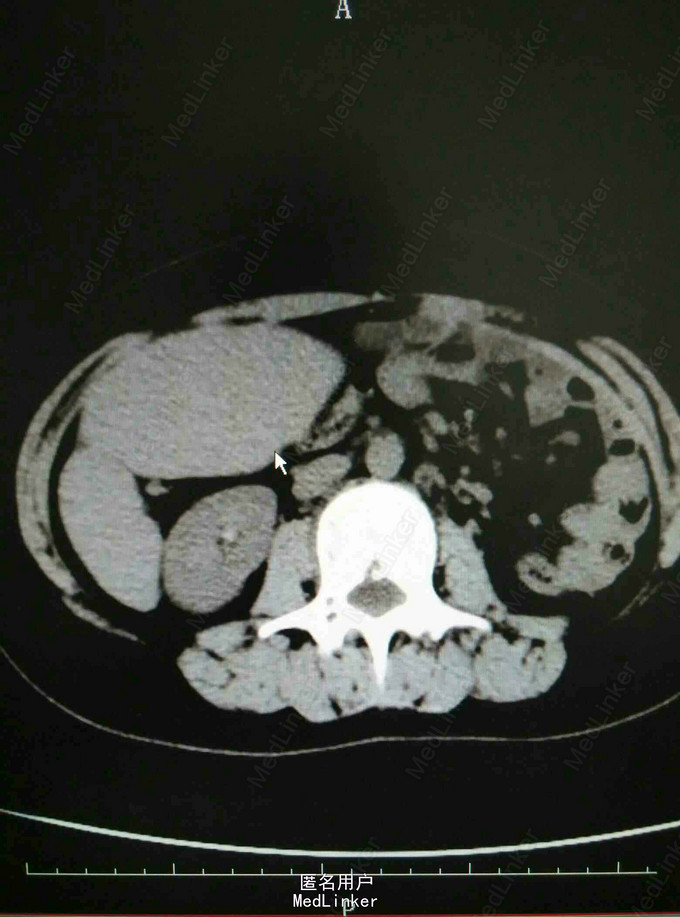

入院诊断:脾机能亢进 处理:全麻下行腹腔镜下脾切除术,术后病理提示慢性脾瘀血。

患者术后恢复良好,嘱出院后加强营养,不适随诊。 讨论:患者曾行先天性膈疝修补术,脾脏的移位是为修补手术影响所致,还是先天形成?